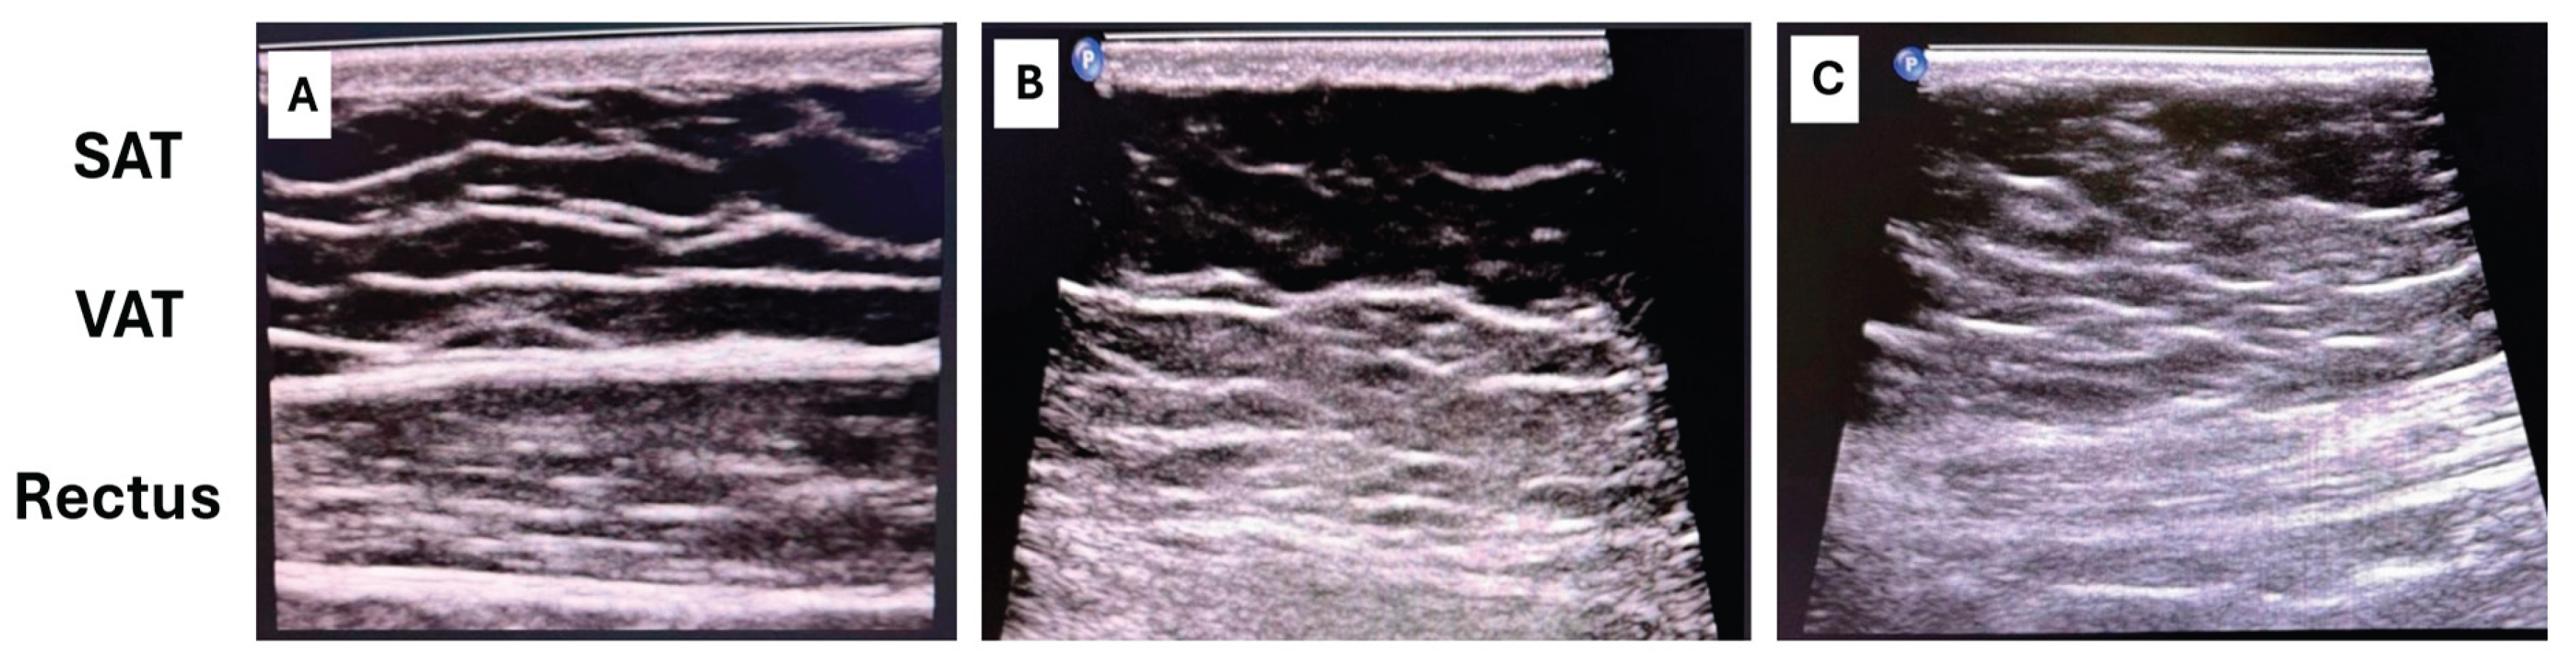

Abdominal Fat Distribution (VAT/SAT ratio + rectus fat ratio) to -20-0 points

Higher visceral adipose tissue (VAT), an altered ratio between subcutaneous adipose tissue (SAT) and VAT, and fat infiltration of the abdominal wall reflect severe metabolic dysfunction, insulin resistance, and ectopic fat deposition [29].

-

Ultrasound represents a practical and low-cost approach suitable for routine clinical assessment [46]: VAT is measured as the distance between the posterior surface of the abdominal muscles and the anterior wall of the aorta or lumbar spine, while SAT is measured from the skin to the linea alba (Figure 4).

Rectus abdominis fat infiltration is evaluated using ultrasound by assessing muscle thickness and echotexture, or by CT cross-sectional imaging when available. Ultrasound-based assessment focuses on increased muscle echogenicity and reduced contractile tissue, which reflect fatty infiltration and fibrotic remodeling.

6.7.3. Interpretation & Thresholds

VAT/SAT ratio

Commonly used research benchmarks include:

• VAT/SAT < 0.4 → favorable fat distribution

• VAT/SAT 0.4–0.7 → intermediate cardiometabolic risk

• VAT/SAT > 0.7 → high visceral fat dominance

At present, no universally accepted quantitative cut-off values exist for rectus muscle fat infiltration. Therefore, assessment is based on qualitative or semi-quantitative criteria, including:

• increased muscle echogenicity compared with adjacent tissues,

• reduced muscle thickness,

• loss of normal fibrillar architecture.

Moderate-to-severe rectus fat infiltration—particularly when associated with increased echogenicity and muscle hypotrophy—has been consistently linked to insulin resistance, impaired glucose uptake, reduced metabolic flexibility, and adverse cardiometabolic profiles, independent of BMI and overall adiposity.

For this reason, rectus fat infiltration is considered a risk-amplifying structural marker, complementing VAT/SAT ratio rather than replacing it.

Within the C.O.R.E. framework, abdominal fat distribution contributes as a structural penalty indicator as follows:

0 points penalty: low VAT/SAT + minimal rectus fat infiltration

–10 points: moderate visceral/ectopic fat distribution

–20 points: high visceral dominance + rectus fat infiltration

6.7.4. Clinical Meaning

Elevated visceral adiposity and rectus muscle fat infiltration are strongly associated with insulin resistance, NAFLD, HFpEF, atrial myopathy, and cardiometabolic disease progression [38]. Importantly, these patterns are common in normal-BMI individuals with high cardiometabolic risk and therefore correct one of the major blind spots of traditional scores.